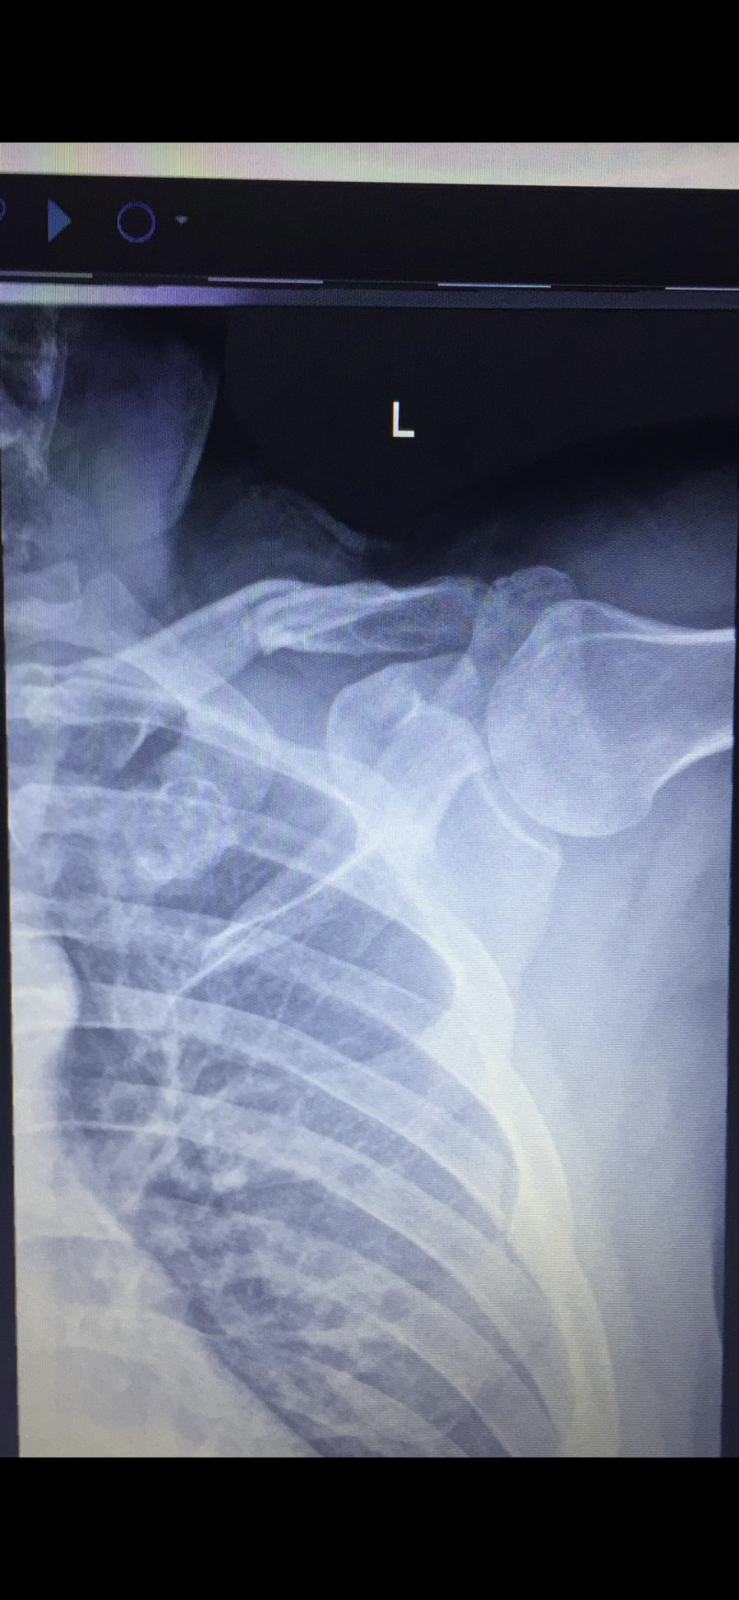

- Nach halben Jahr Heilung und 3 Monaten wieder fahren im Bikepark Drop bei letzter Abfahrt falsch gemacht und Oberarmkopf gebrochen (vermutlich blöd auf dem Ellenbogen gelandet)

Habe auch Typ 3. Hattest du auch solche Schmerzen direkt aus der Hölle nach der OP?Ich hatte bisher nur eine Schulterecksgelenksprengung Tossy 3 / Rockwood 4, eine Beckenprellung und 3 Monate Knieschmerzen nach einem Sturz. Was das war kann ich nicht sagen, war nicht beim Arzt![]()

Nö, überhaupt nicht. Ich habe keine einzige Schmerztablette genommen. Bin am Tag nach der OP schon nachhause gegangen.Habe auch Typ 3. Hattest du auch solche Schmerzen direkt aus der Hölle nach der OP?